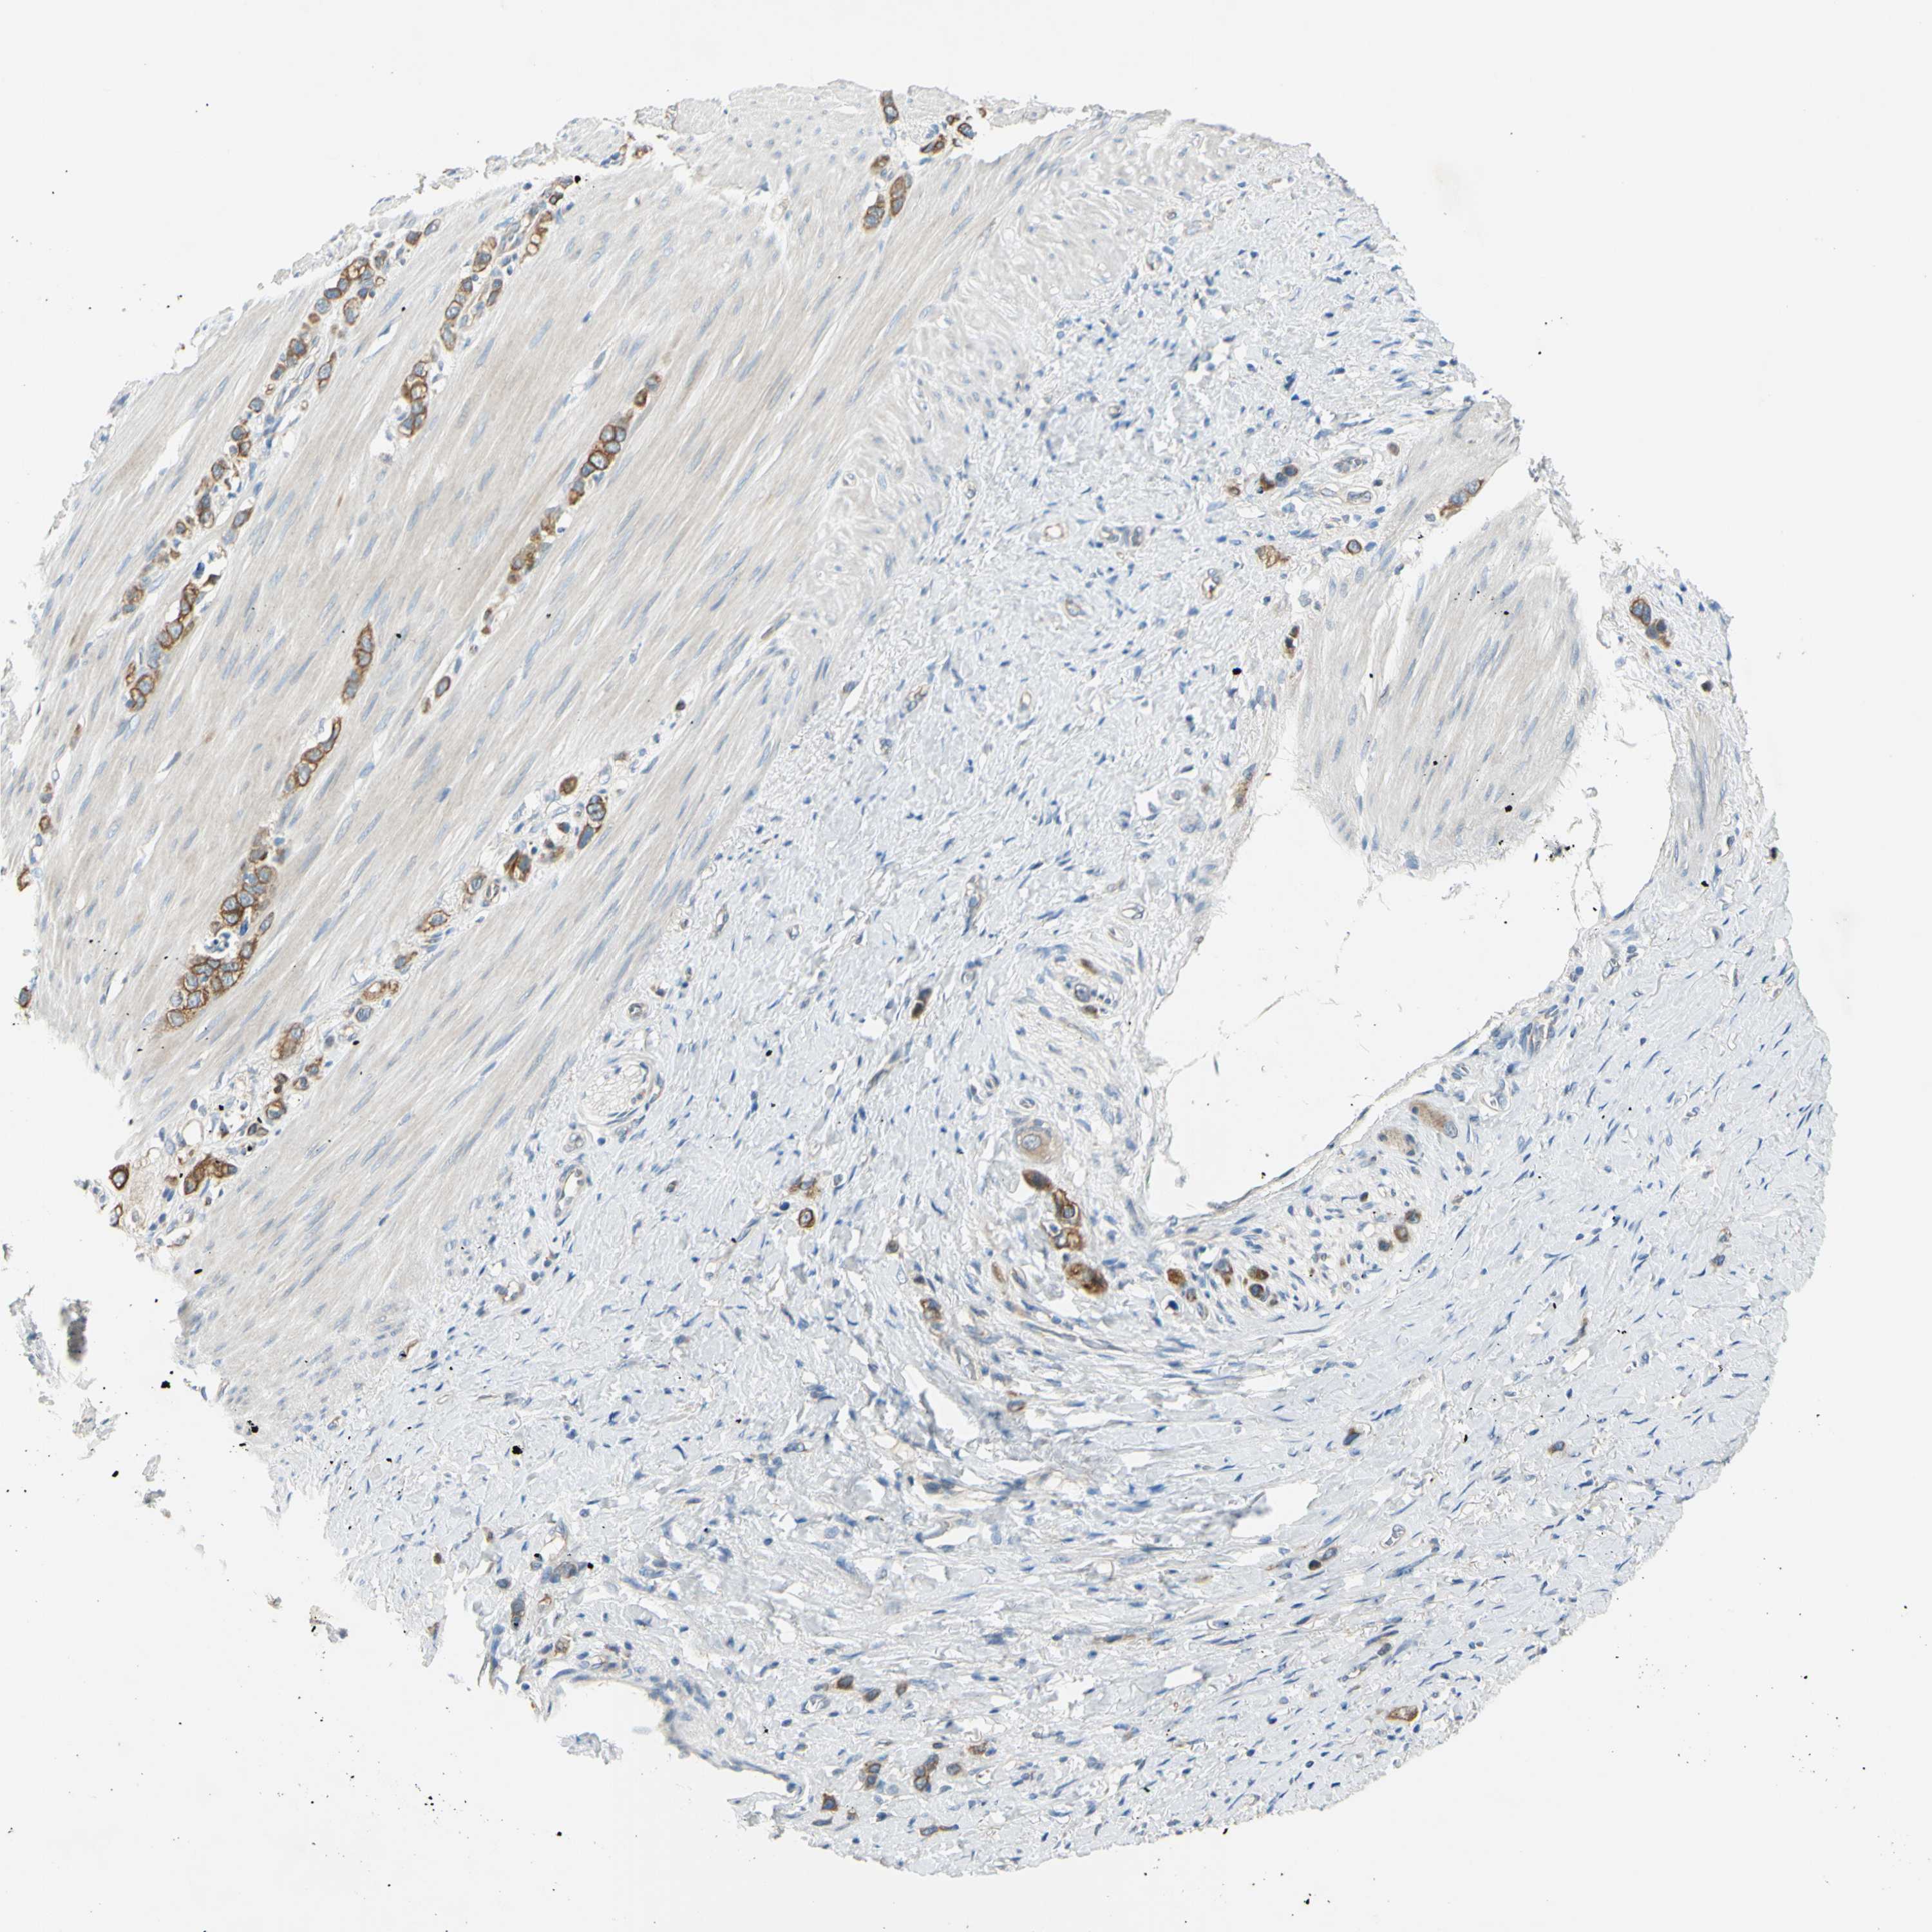

STOMACH CANCER - Protein expressioni

A mouse-over function shows sample information and annotation data. Click on an image to view it in a full screen mode. Samples can be filtered based on level of antibody staining by selecting one or several of the following categories: high, medium, low and not detected. The assay and annotation is described here.

Note that samples used for immunohistochemistry by the Human Protein Atlas do not correspond to samples in the TCGA dataset.

Antibody stainingi

Antibody staining in the annotated cell types in the current human tissue is reported as not detected, low, medium, or high, based on conventional immunohistochemistry profiling in selected tissues. This score is based on the combination of the staining intensity and fraction of stained cells.

Each image is clickable and will lead to virtual microscopy that enables deeper exploration of all samples and also displays staining intensity scores, fraction scores and subcellular localization as well as patient and tissue information for each sample.

Antibody HPA009309

Antibody CAB010757

Staining

High

Medium

Low

Not detected

Intensity

Strong

Moderate

Weak

Negative

Quantity

>75%

75%-25%

<25%

None

Location

Nuclear

Cytoplasmic/membranous

Cytoplasmic/membranous,nuclear

Adenocarcinoma, NOS

Adenocarcinoma, High grade